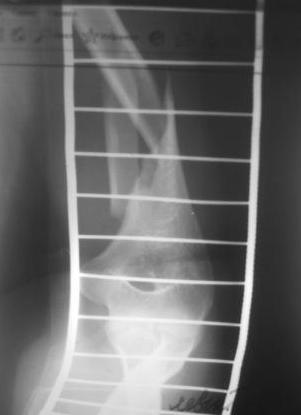

Re: Перелом н\3 плечевой кости. Тактика лечения?

Перелом нестабильный, тактика - если позволяет сосояние больной, оперативное лечение. Как пример см. ниже, можно без скобы - стяжки с ЭПФ.

Представленный способ, функциональный, данная больная в качестве внешней иммобиллизации в течение 3-х недель полльзовалась косыночной повязкой, востановление функции плеча полное. Правда травма изолированная, но операция выполнялась через три недели после травмы, тот час после обращения ко мне - иногородняя.